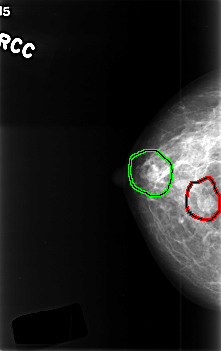

C_0386_1.RIGHT_CC

FILE: C_0386_1.RIGHT_CC.OVERLAY

TOTAL_ABNORMALITIES 2

ABNORMALITY 1

LESION_TYPE MASS SHAPE OVAL MARGINS CIRCUMSCRIBED

ASSESSMENT 3

SUBTLETY 5

PATHOLOGY BENIGN

TOTAL_OUTLINES 1

BOUNDARY

ABNORMALITY 2

LESION_TYPE MASS SHAPE LOBULATED MARGINS CIRCUMSCRIBED